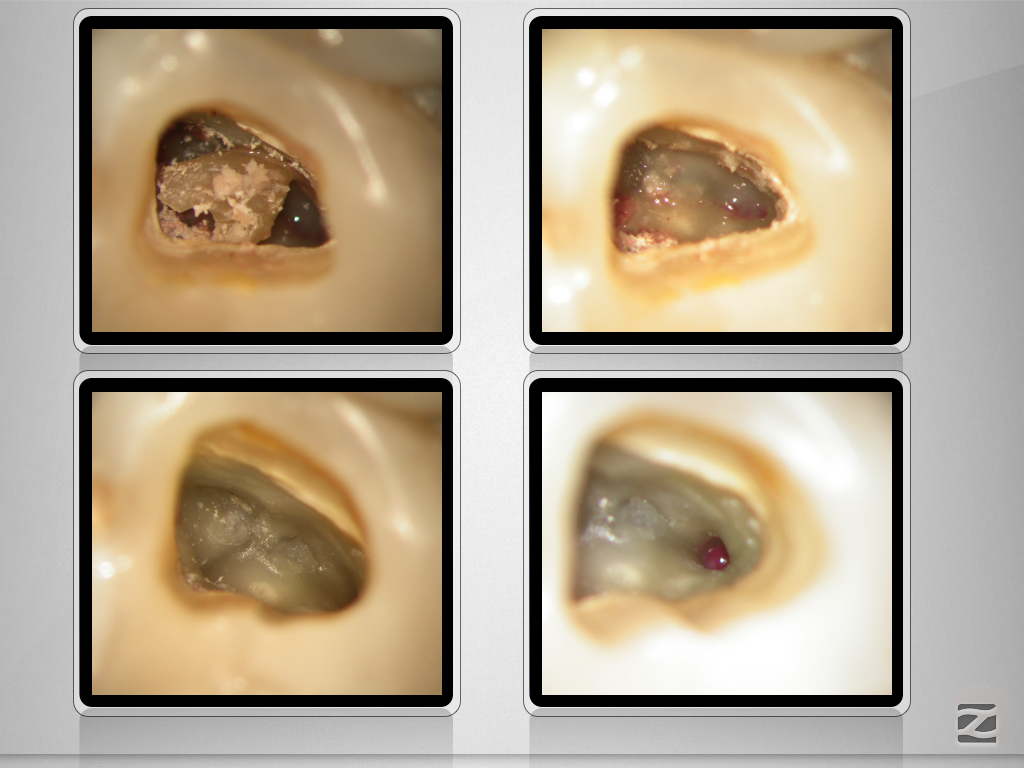

Vitales Gewebe – apikale Aufhellung